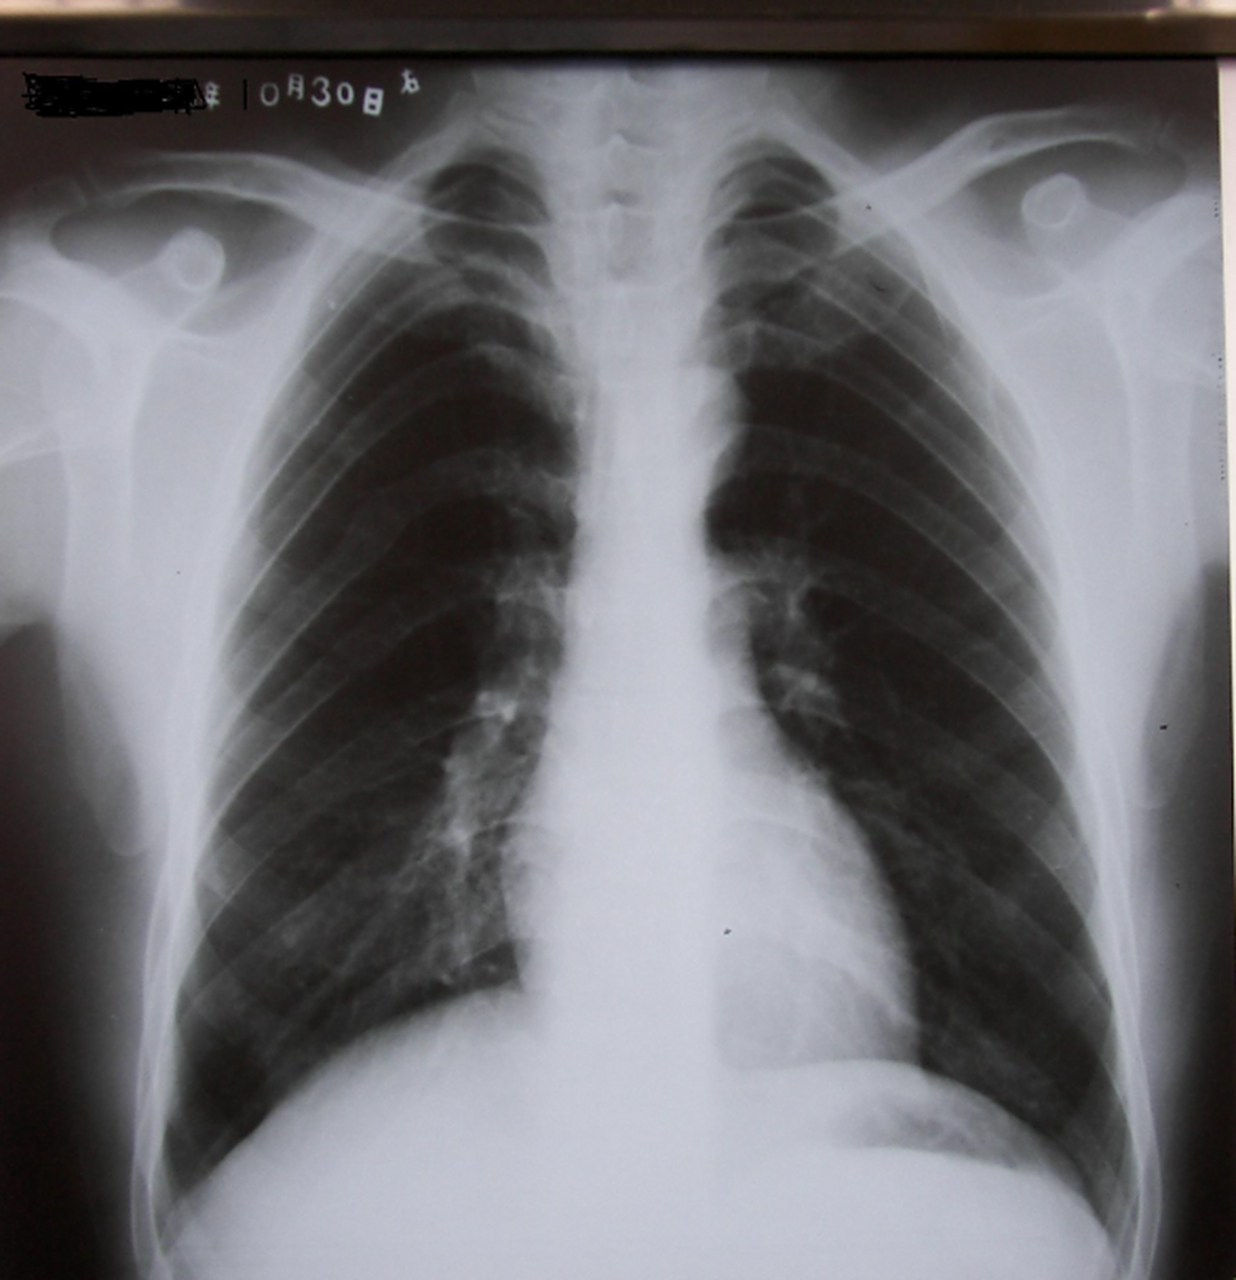

肺有片状阴影是怎么回事

论肺ct的重要性,最近大叶性肺炎,重症肺炎多见,下图胸片对比右侧相对

大叶性肺炎是一种在远端气腔内发展的炎性病变,具有其独特的特点